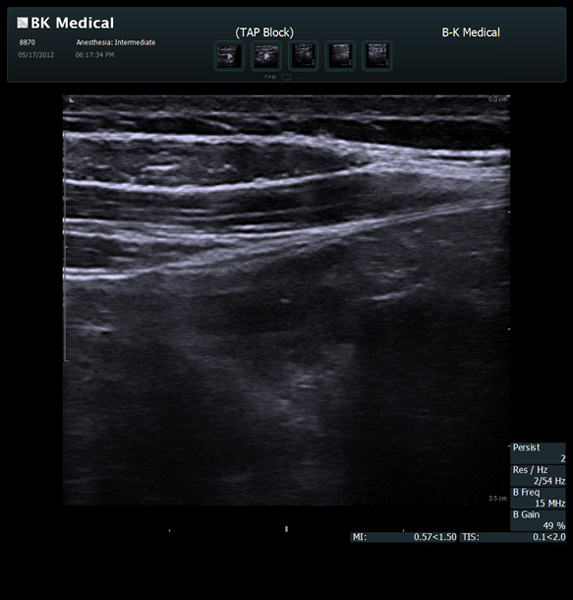

Enhanced Needle Visibility with Innovative X-Shine

X-Shine needle visualization option enhances the needle’s appearance in real time during in-plane procedures.

Transducers Designed for Guidance

BK Medical offers high-frequency linear transducers, imaging from 18-2 MHz for upper and lower extremities, and curved array abdominal transducer 8820e for special deep nerves or paravertebral/spinal applications. Our transducers provide superb detail that makes it easy to see your needle during procedures.